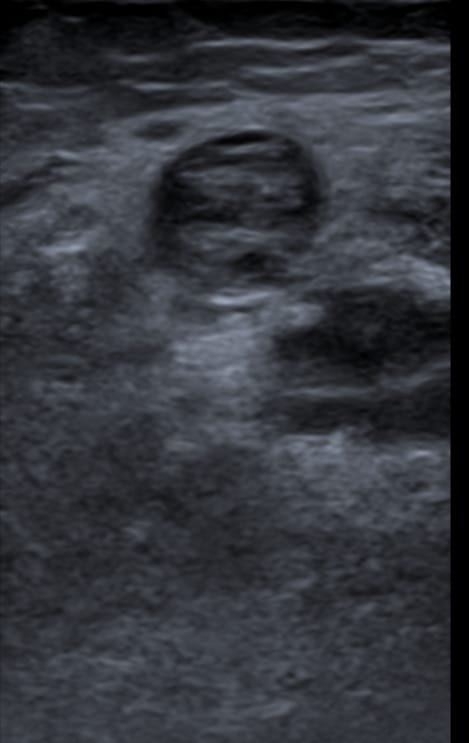

ECO MMIIII: se rastrea desde región femoral hasta el tobillo en la que no se aprecia la desaparición de la vena poplítea a la compresión con el ecógrafo.